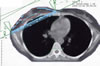

Mammakarzinom